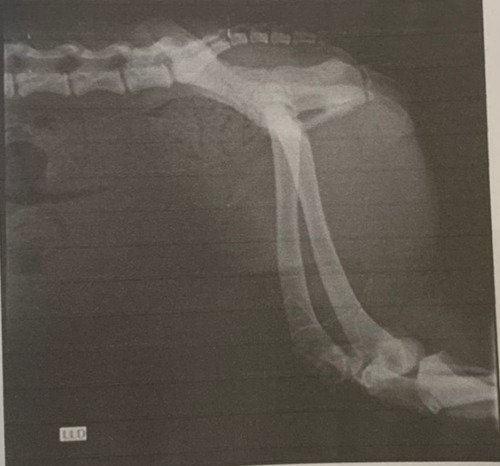

Lalinha é uma cachorrinha cuidada por um protetor onde existem vários animais. Em novembro, infelizmente, ela sofreu um atropelamento. Uma de suas patas traseiras teve fratura exposta e dilaceração da pele. Levamos ela para uma urgência veterinária, pois ela estava sangrando muito, e não parava de tremer.